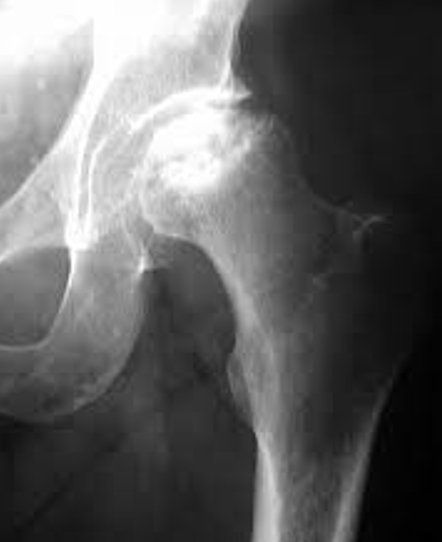

Pour les prothèses de hanche et de genou, nous préférons une hospitalisation courte afin d’optimiser les protocoles de récupération rapide et la surveillance du patient dans les 24-48h après l’opération.

Ainsi la durée d’hospitalisation pour une prothèse de hanche est de 1 à 2 jours et pour une prothèse de genou de 2 à 3 jours.